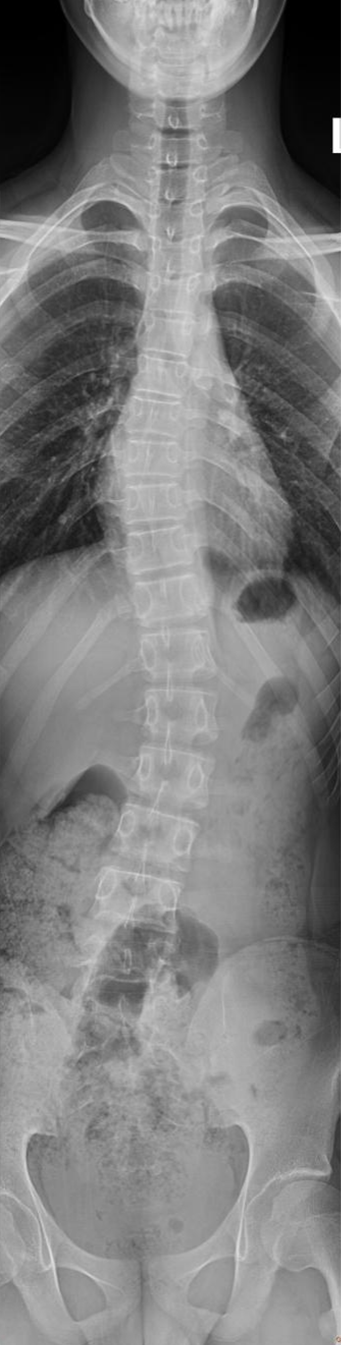

脊柱全长DR摄影技术是一种先进的检查方式,解决了全脊柱不能一次成像的问题,经过4-5次的曝光后,可以完成脊柱全长的站立负重位摄影,通过拼接技术,将多张X线片进行拼接,形成一个完整的脊柱全长影像,这种技术可以更直观、更全面、更准确的观察脊柱的整体形态,帮助评估侧弯的程度,极大的方便了病情的分析,为临床的诊断和治疗提供了重要的影像学依据。对侧弯的治疗方式和治疗后的评估提供了极为重要的参考价值。

脊柱全长DR摄影

脊柱全长DR摄影技术的应用:

1、脊柱侧弯:显示侧弯的角度和弯曲的部位,根据弯曲的程度制定治疗方案。

5、脊柱侧弯矫正效果的评估,定期的复查,医生可以观察侧弯程度的变化,评估矫正的效果,从而调整治疗方案。